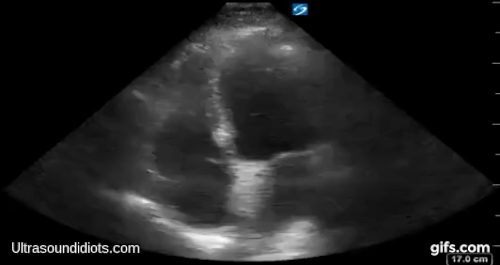

Parasternal Exam 3